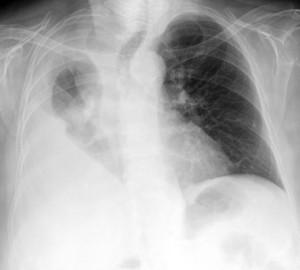

Ante un paciente que acude a urgencias y presenta síntomas y signos de patología torácica está indicada la realización de una placa simple de tórax. Es una prueba sencilla y rápida y que además aporta mucha información. Con ella, se pone de manifiesto problemas respiratorias como derrames pleurales o atelectasias, cardiacos como una hipertrofia de ventrículos, mediastínicos (masas, neumomediastino), así como patología ósea de las costillas y las vértebras.